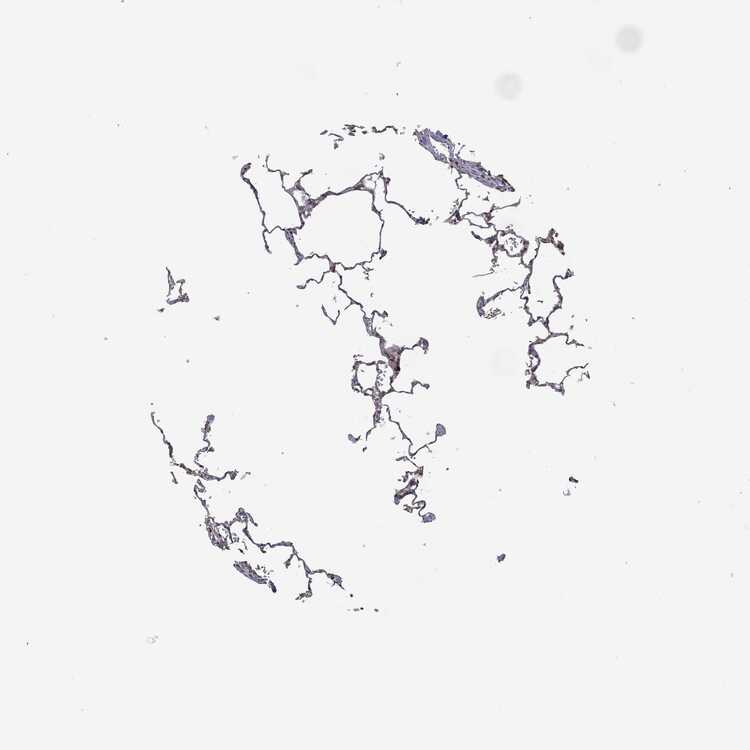

LUNG - Antibody stainingi

Antibody staining in the annotated cell types in the current human tissue is reported as not detected, low, medium, or high, based on conventional immunohistochemistry profiling in selected tissues. This score is based on the combination of the staining intensity and fraction of stained cells.

Each image is clickable and will lead to virtual microscopy that enables deeper exploration of all samples and also displays staining intensity scores, fraction scores and subcellular localization as well as patient and tissue information for each sample.

Antibody HPA005695Antibody CAB022068Antibody CAB035999Antibody CAB080052Antibody CAB080054Antibody CAB080098

Alveolar cells Not detectedLowMediumMediumNot detectedNot detected

Macrophages LowNot detectedMediumNot detectedNot detectedNot detected